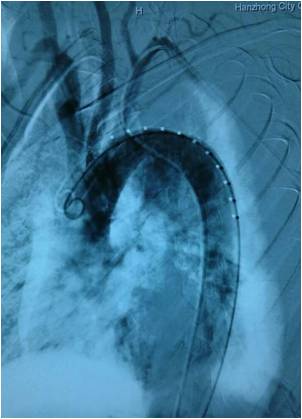

此例病人是由车祸导致的外伤性主动脉瘤,入院时生命危在旦夕。西京医院杨剑教授主刀,经过90分钟的奋战,完美的为患者植入了彩神在线网信彩票-彩神通免费版下载-彩神8争霸vlll-彩神购彩购彩大厅-彩神软件陆立根免费版-彩神ll争霸3-彩神ll彩神8-彩神ll争霸彩票-拼搏在线彩神网网页版科技主动脉单分支覆膜支架系统。术后造影显示,病人主动脉弓各分支血管的血流通畅,支架形态良好,患者生命因此得以成功挽救。

图1 术后病人的CTA影像 图2.病变血管造影

图3 支架释放后形态 图4. 植入支架后造影